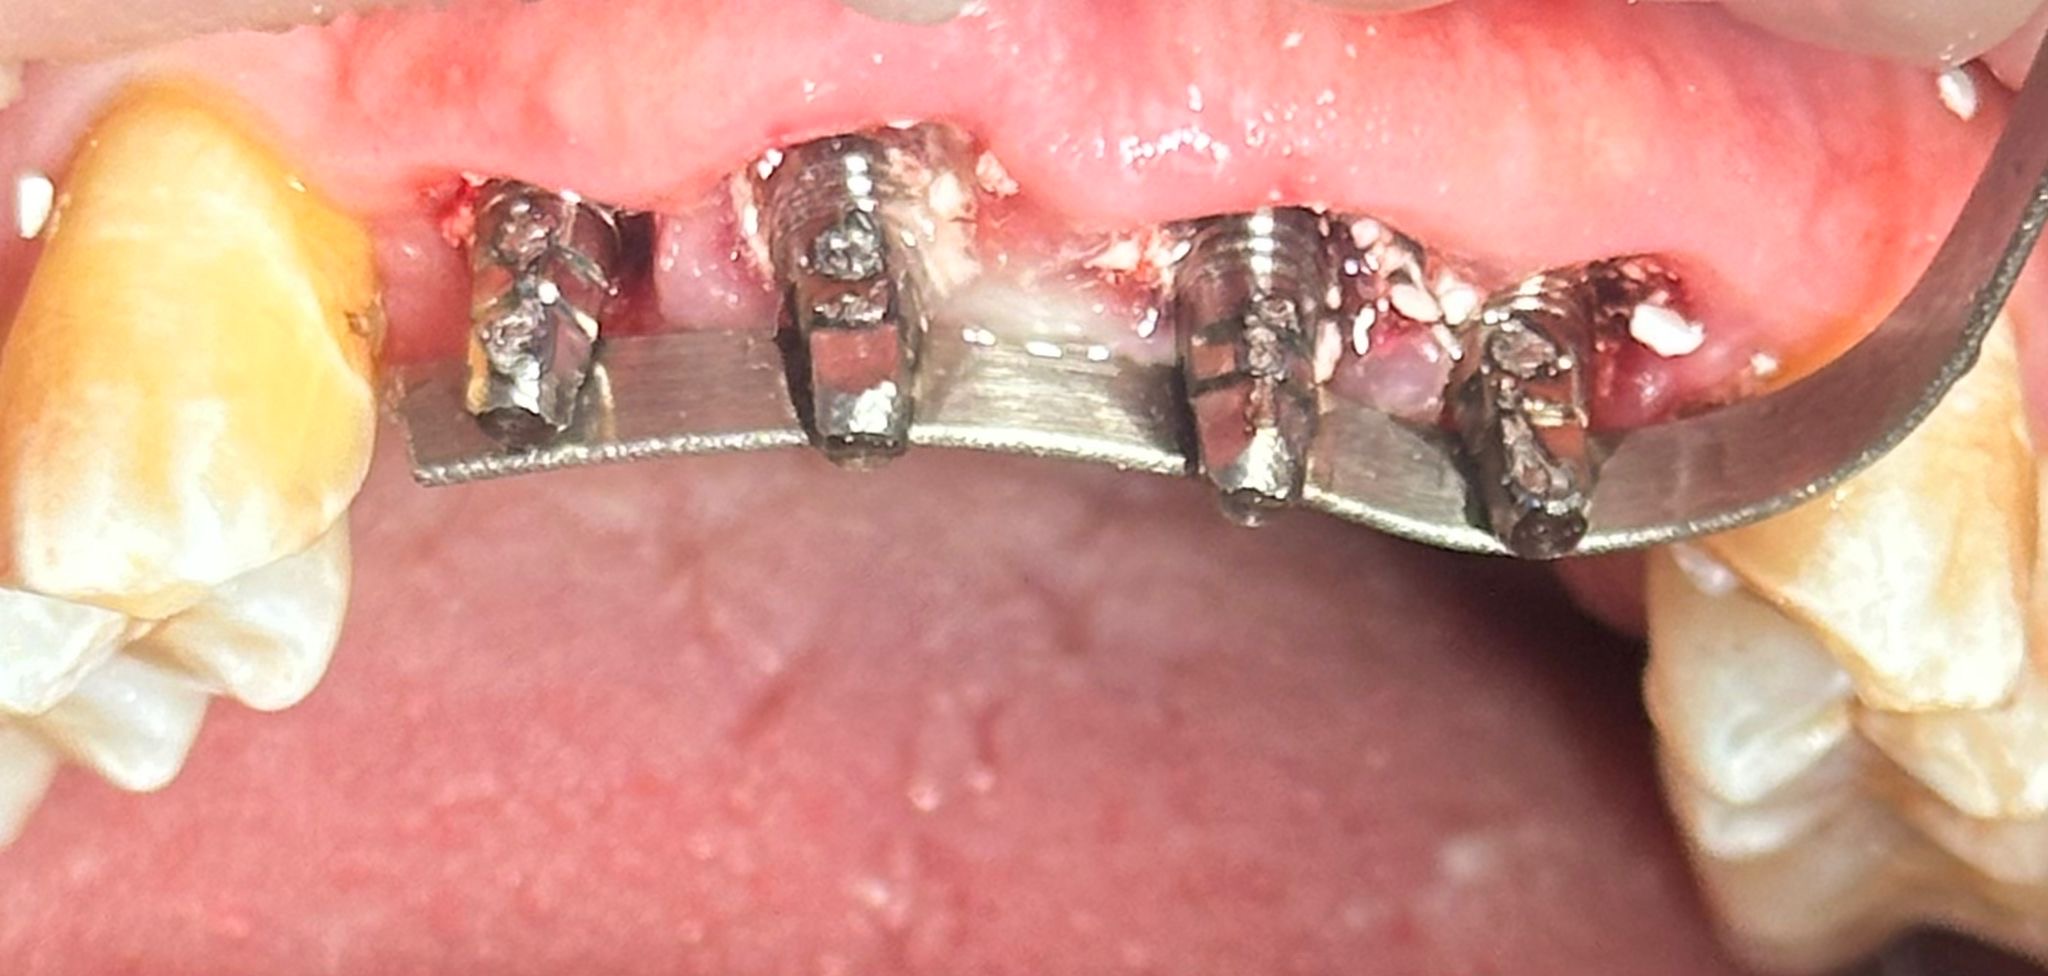

Realizamos la extracción de los cuatro incisivos superiores y, en el mismo acto quirúrgico, colocamos cuatro implantes de anclaje basal de 23 mm, buscando apoyo en el hueso cortical, el hueso más denso y estable. Además, se realizó una soldadura intraoral para rigidizar el conjunto y aportar máxima estabilidad desde el primer momento.

Para nuestro equipo clínico de la clínica dental Dr. Darío Castro – Dental Office esto supone la carga inmediata real.

Se colocó un provisional de larga duración para controlar la evolución de los tejidos y, como suele ocurrir en este tipo de casos, el paciente refirió molestias mínimas y una mejoría inmediata en función, estética y bienestar.